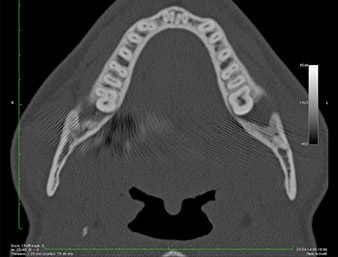

On voit sur l’image 3D (tomographie volumétrique numérique) que le reste radiculaire est en position disto-caudale au niveau de la transition de la partie horizontale vers la partie ascendante de la mandibule (Fig. 2).

de réussite. L’OPG ayant révélé que le reste radiculaire était très proche du nerf alvéolaire inférieur, une tomographie volumétrique numérique a été effectuée en plus (6).